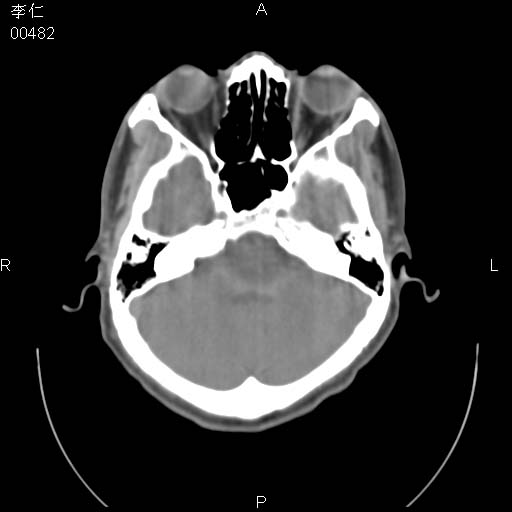

患者男,45岁。于二月前发现左眼稍肿,去看眼科,查肾功(—),来查ct,我看到的是左侧上眼睑内低密度影,ct值是-600到-700hu。

是气体 前组筛窦发育过度所致,如果有外伤就不排除骨折

是一个副鼻窦的正常变异,脂肪瘤的密度不可能这么低,-600到-700.

只是空气而已,属正常ct表现。

副鼻窦的正常变异